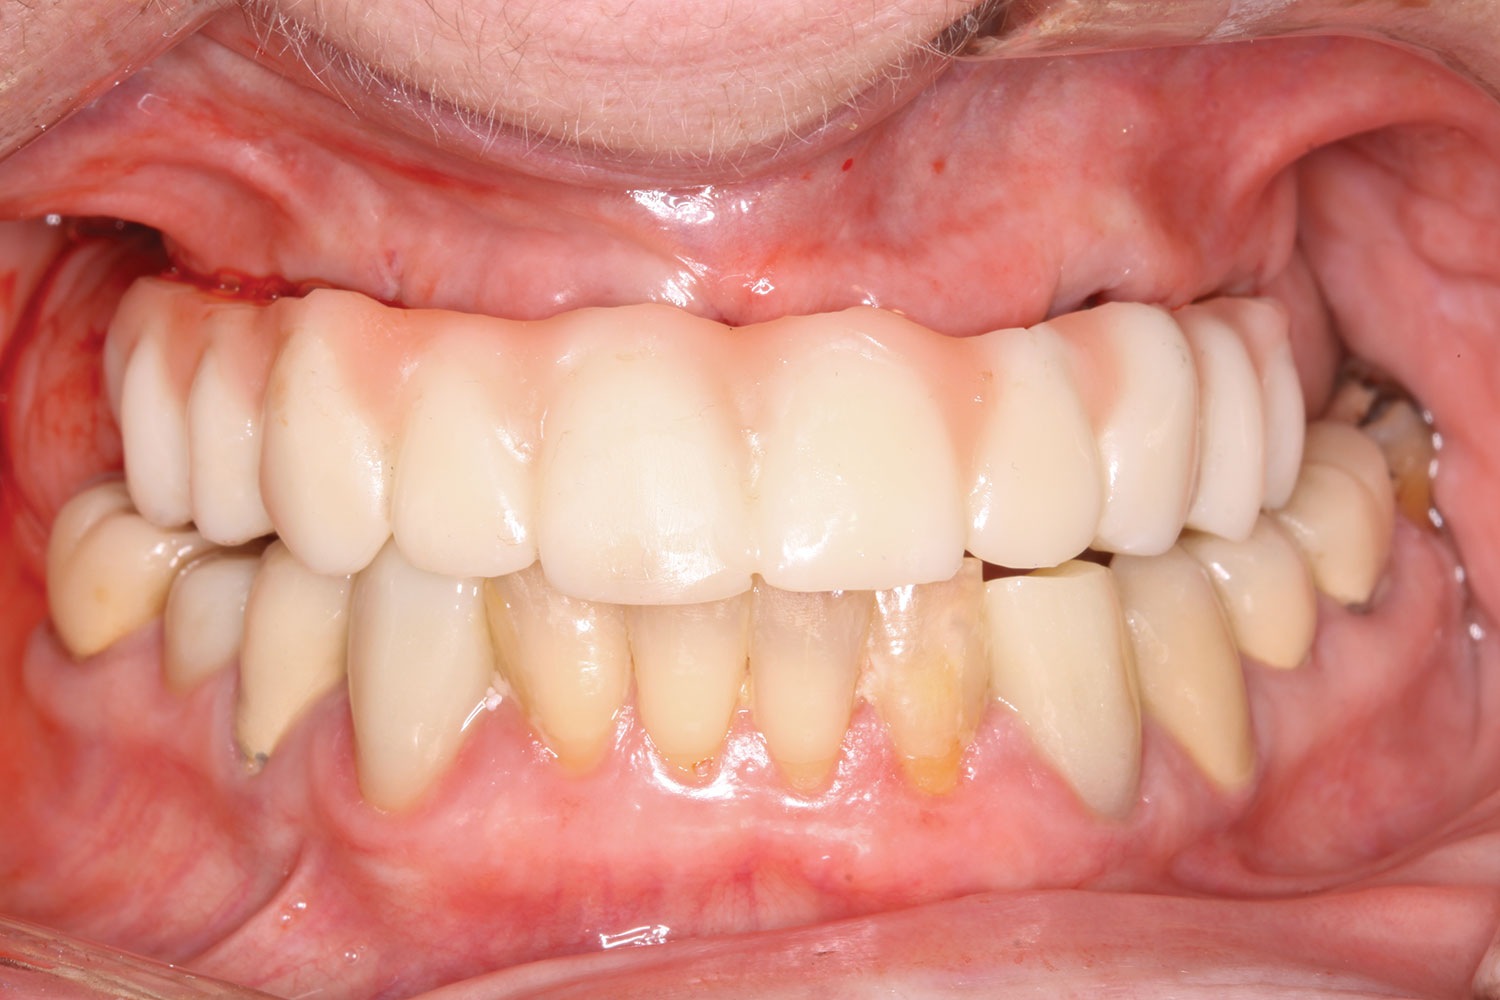

Fig 18. Implants and provisional maxillary prosthesis in place, the same day as surgery.

Figure 18

Fig 19. The patient’s smile display, the same day as surgery.

Figure 19

Fig 38. Maxillary and mandibular provisional restorations inserted, day of surgery.

Figure 38

The prosthesis fit precisely on the multi-unit abutments, and multi-unit screws were used to secure the prosthesis in place at 20 Ncm (Figure 18 through Figure 20). The screw-access holes were filled, and the patient was instructed on dietary restrictions and adherence to a soft diet. Instructions for oral hygiene were given, and the patient was advised to use a water flosser daily. Analgesics included ibuprofen 800 mg, and for antibiotics, amoxicillin 500 mg three times a day was prescribed.

Postoperative x-rays documented the full seating of the prosthesis on the multi-unit abutments (Figure 21 and Figure 22). The patient returned at 1 week postoperatively for a follow-up visit and to review home care. She remarked that the restoration was comfortable and that she was free of discomfort and extremely pleased with the makeover she received in one day.

The completed prosthesis was then screwed directly onto the multi-unit abutments with Rosen screws with no ti-bases and torqued to 20 Ncm. Screw-access holes were filled, and no occlusal adjustment was necessary. The fit of the prosthesis was precise and stable and the phonetics of the patient was ideal. The patient was overwhelmed by the significant esthetic improvement with this set of teeth in place.